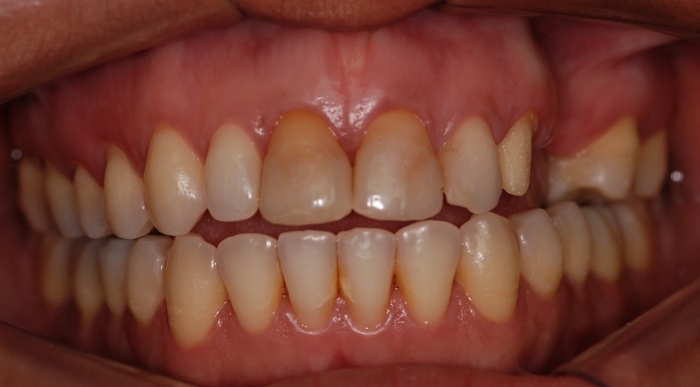

Imagens iniciais observando importante perda óssea e dentária superior